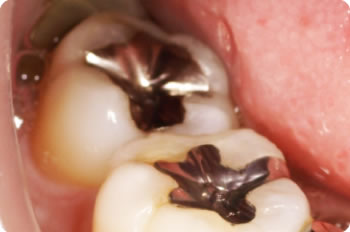

1本にハイブリッドインレーを詰めました。治療回数2回、治療期間は約1週間でした。